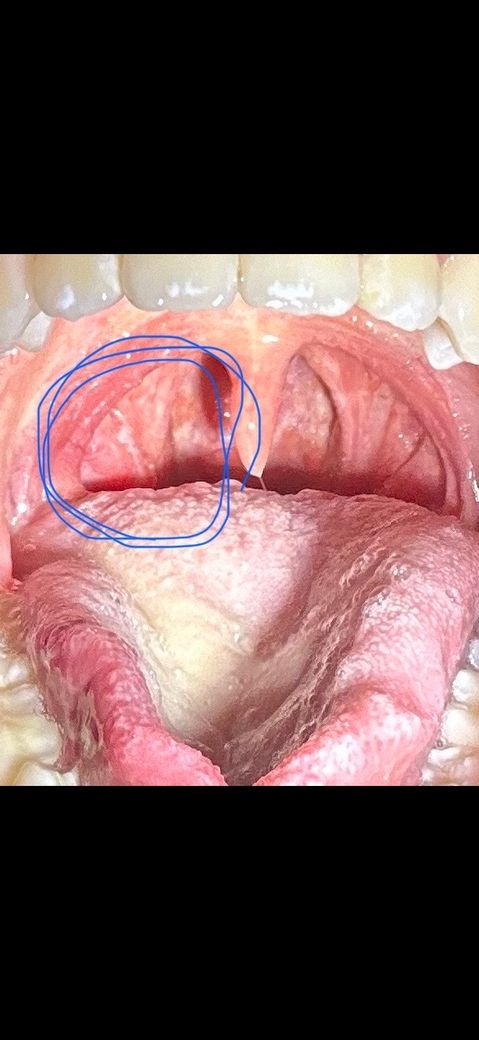

사진상 왼쪽 목구멍부터 목 안쪽까지 아픕니다

이틀 전에 연어를 먹다가 가시를 삼켜서 좀 아픈 것 같아서 신경을 쓰다보니까 진짜 아픈 것 같았습니다. 그래서 다음날 바로 내과에가서 위내시경 검사를 했는데 가시도 없고 이상도 없다고 해서 이비인후과에 가서 목구멍을 봤는데 가시는 없고 염증이 있다고 해서 약을 받아서 먹고 있습니다. 근데 점점 침과 음식을 삼키기 힘들어지고 침삼킬때 귀도 아프고 턱도 뭔가 불편해져서 걱정이 됩니다. 그래서 입 안을 사진을 찍어봤는데 어떤 병인것 같나요?? 가시가 있을 가능성이랑 심각한 병일 가능성이 있을까요???

• 1번 째 사진